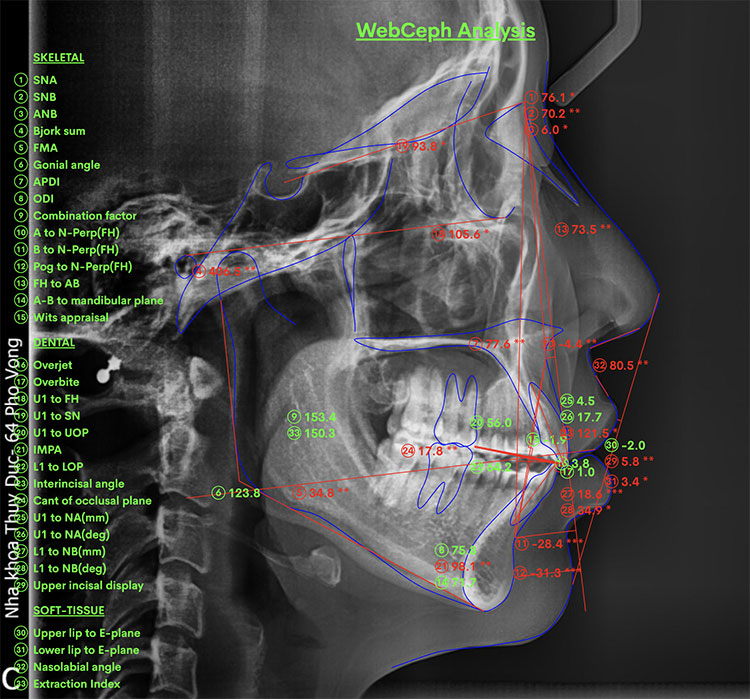

X Quang

Trước |

Sau